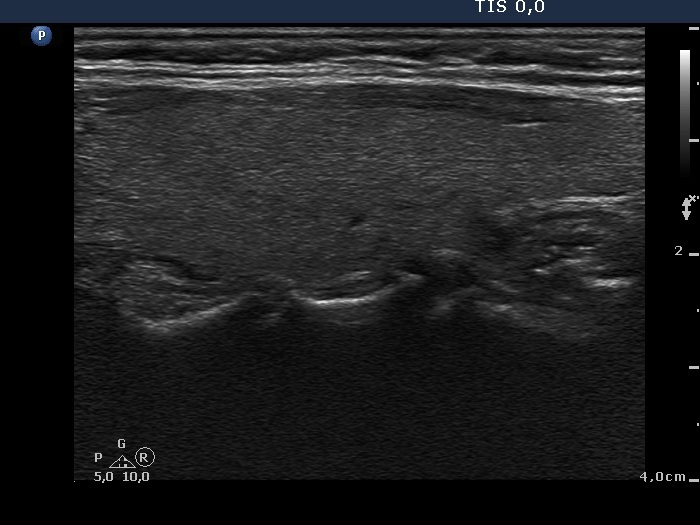

Oxyphilic adenoma - Case 6. (ultrasonographic picture 7)

Left lobe, longitudinal scan.